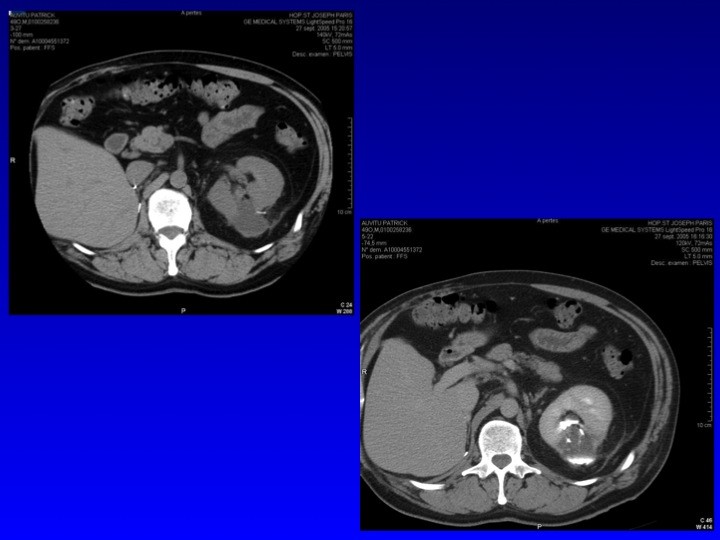

- Nos échecs

Nathalie RIOUX LECLERCQ (Rennes), Nicolas GRENIER (Bordeaux), Hervé BAUMERT (Paris)